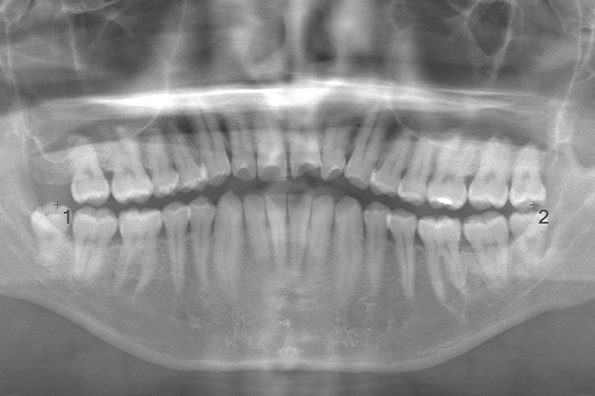

初診時の主訴は下顎左右の歯肉に痛みがあるとのことでした。原因は上顎の7番目の歯が下顎の歯肉に噛みこんでることでした。そのため、矯正を始める前に親知らずの抜歯を行いました。 パノラマと呼ばれる二次元的なレントゲンでは、上下とも縦にはえているように見えて簡単そうですが、三次元的なCTを見ると下顎の親知らずが舌側に傾いていて、上顎の親知らずは歯ぐきに完全に埋まっていました。下顎の親知らずが舌側に倒れているケースは、真横にはえているケースよりも難しい場合があります。 また、上顎の親知らずが歯ぐきに埋まっていて、口が小さい方の場合は抜くのが難しくなります。今回は術前にCTを撮り、事前にしっかりと診断ができたためスムーズに抜歯を行うことができました。 |

CASE 17

基本情報

| 年齢・性別 | 18歳・男性 |

|---|---|

| 主訴 | 矯正を開始する前に左下と左上の親知らずを抜きたい |

| 抜歯期間 | 約1時間 |

| 抜歯費用 | 1本22,000円×2本 合計44,000円 (2022年10月現在) |

| 抜歯内容 | 完全埋伏抜歯 |